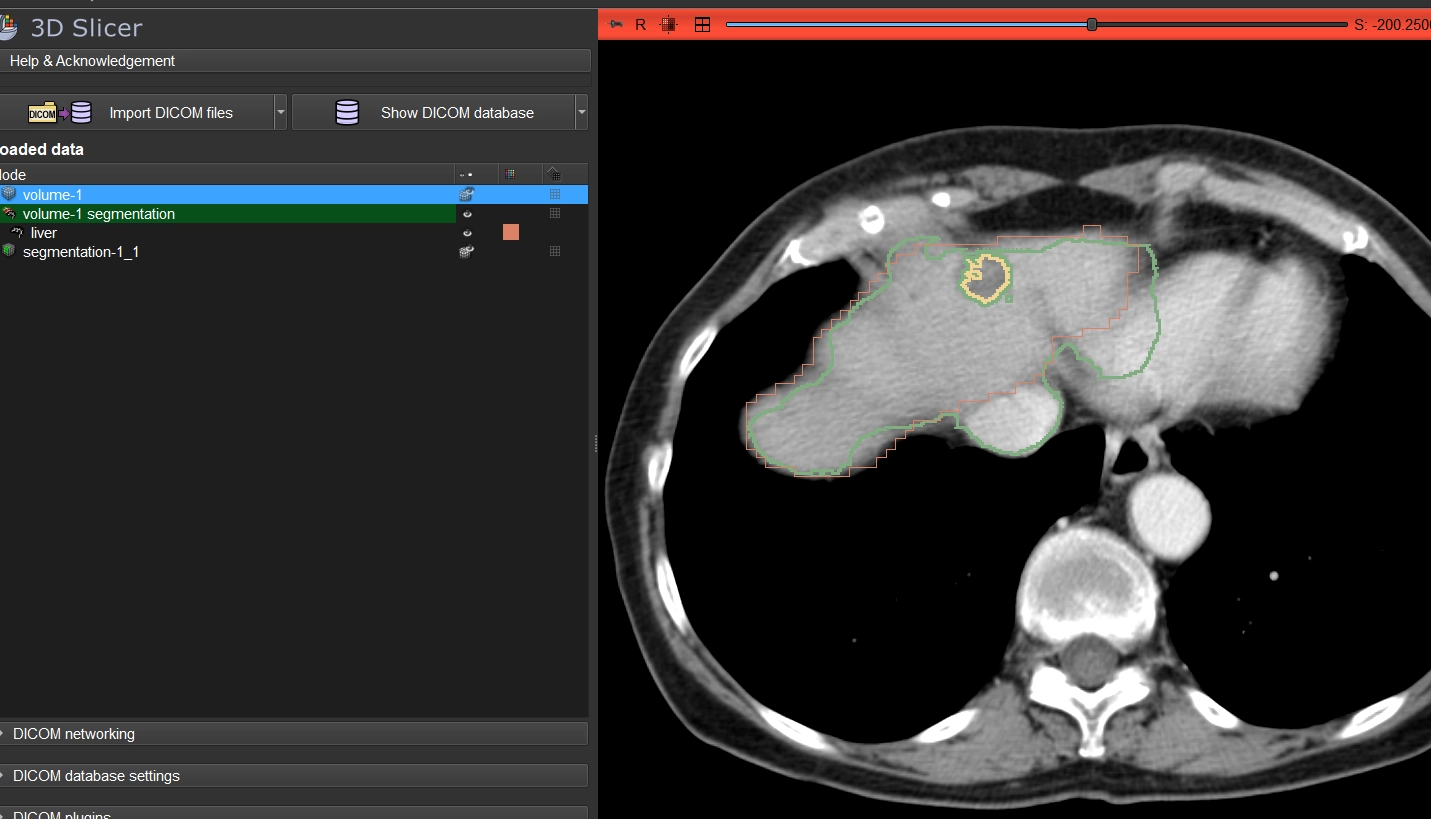

在 3D Slicer 中完成了完整流程:

- 导入CT数据 + AI分割结果(TotalSegmentator)

- 使用 Segment Editor 进行基础修正(Scissors / Paint)

- 与官方标注进行叠加对比(颜色区分 + 透明度控制)

AI结果 → 人工修正 → 对比答案 → 识别误差